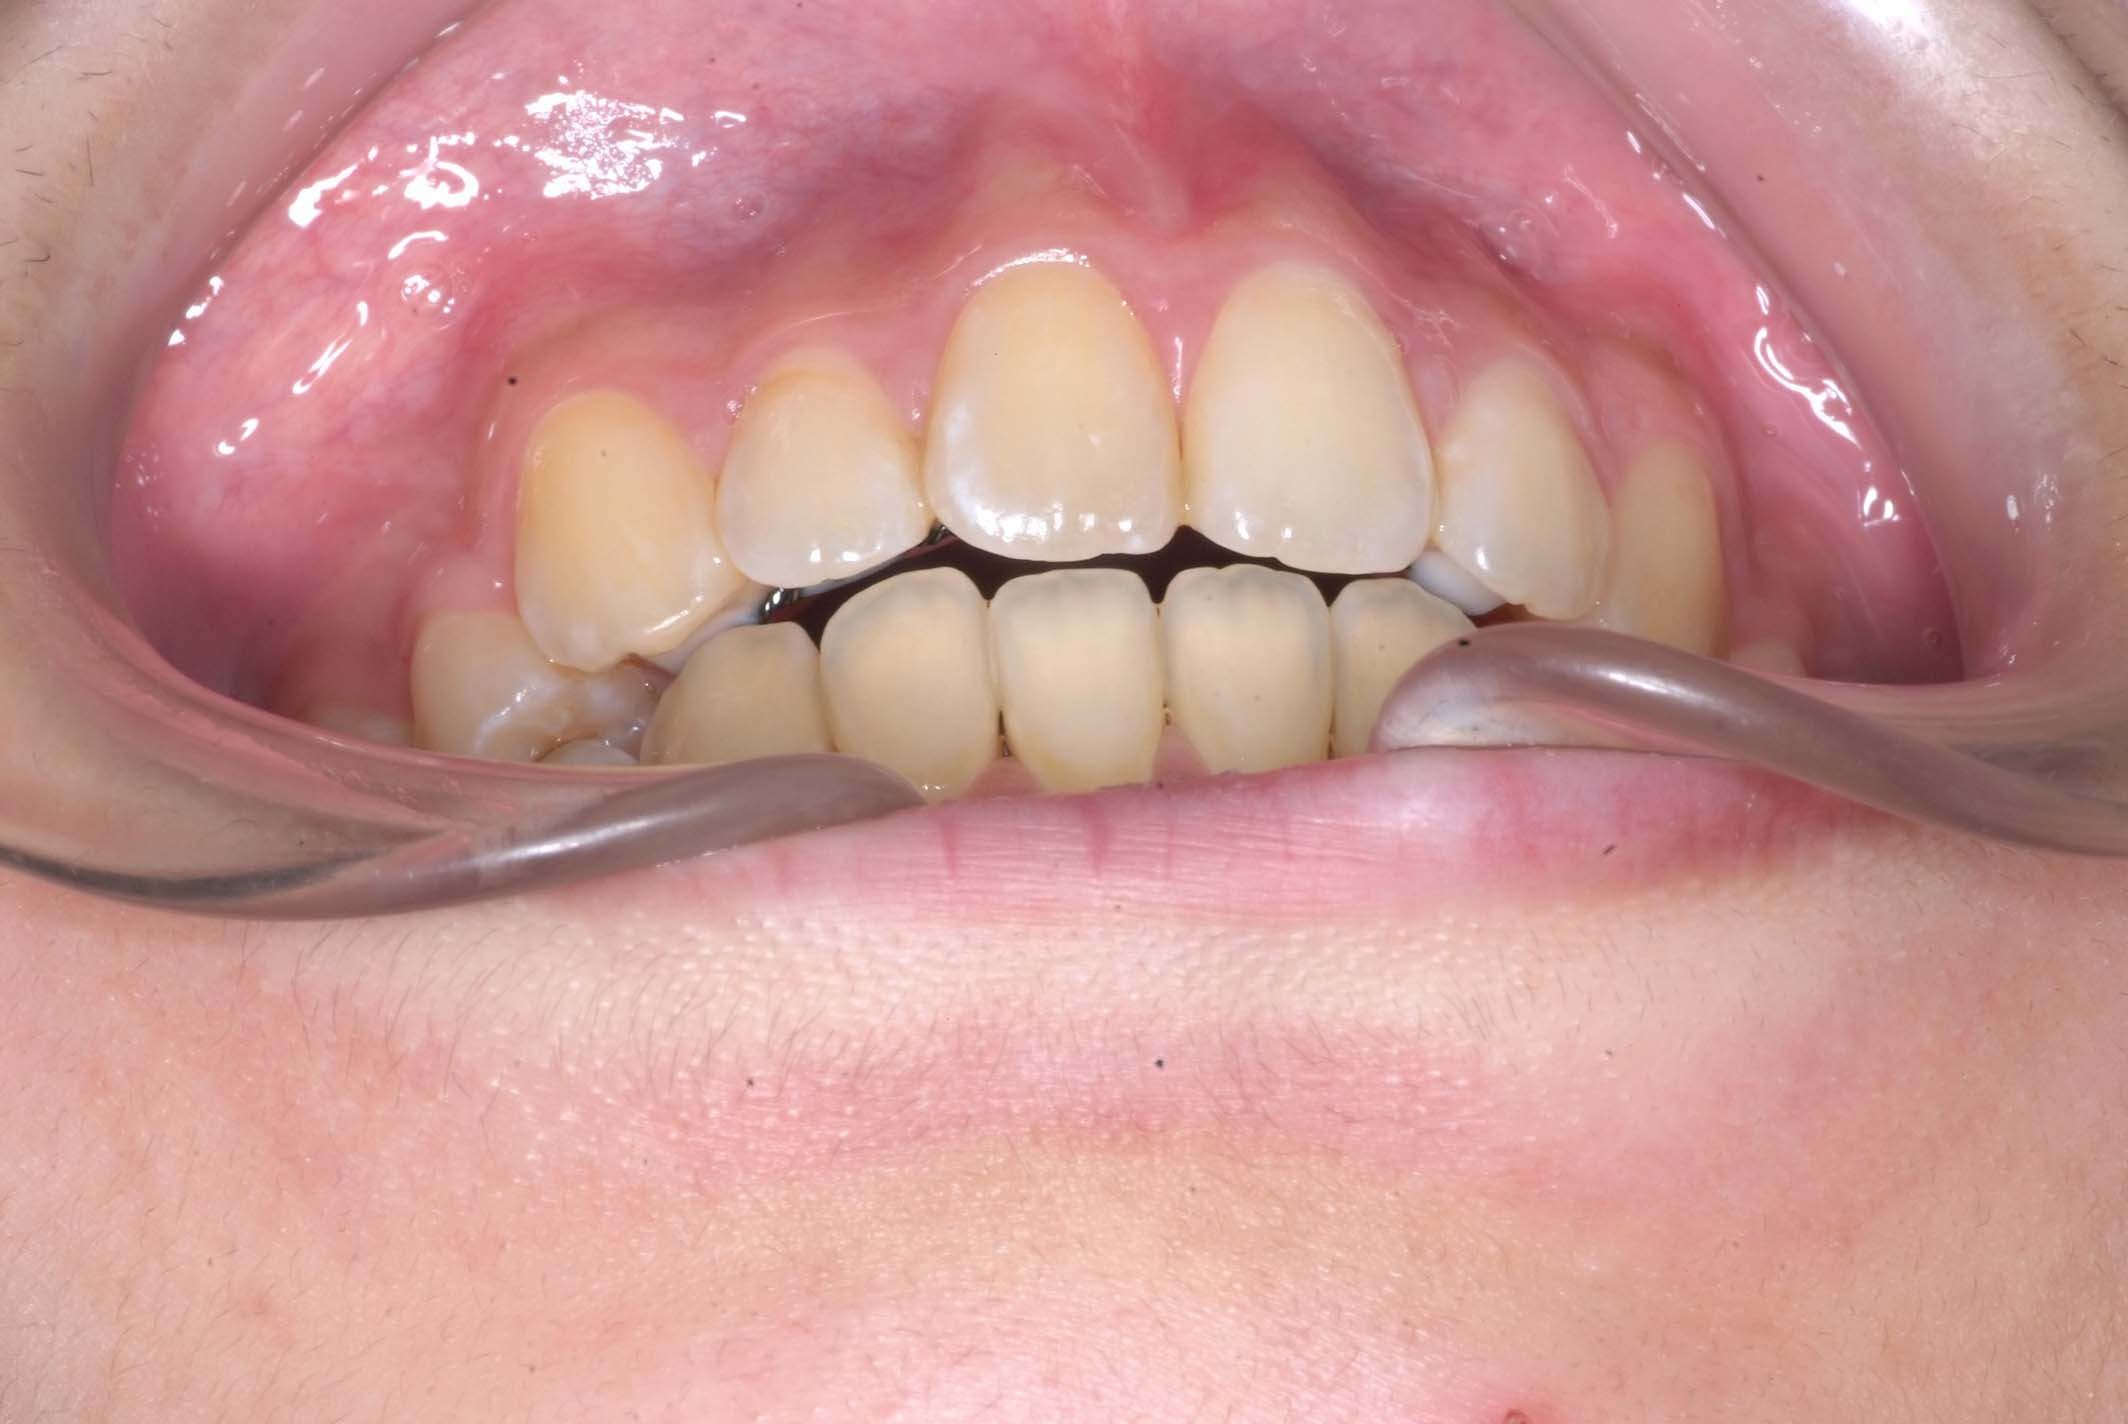

初診時年齢8才の女子で、前歯部開咬を気にして来院されました。

検査の結果、前歯部開咬と正中離開と上下顎前歯唇側傾斜を伴うアングルⅡ級1類不正咬合と診断しました。

前期治療は、リンガルアーチで正中離開を改善し、その後は歯列矯正用咬合誘導装置(マイオブレース)を使用して舌のトレーニングを行いました。後期治療は、上下左右4番を抜歯の上、セルフライゲーションブラケット装置(クリアティ・ウルトラ)で行いました。治療期間は前後期合わせて6年6ヶ月でした。通院回数:60回。